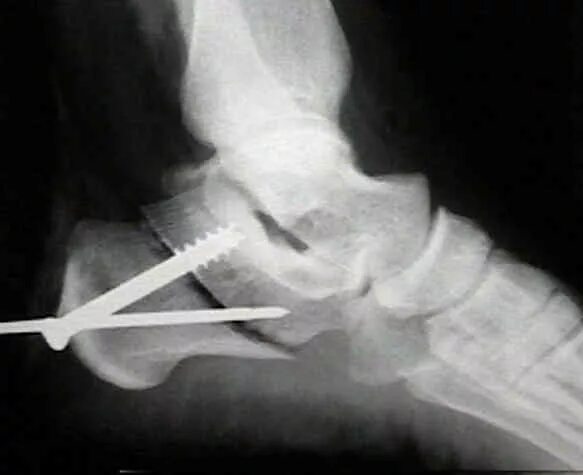

Пяточная остеотомия